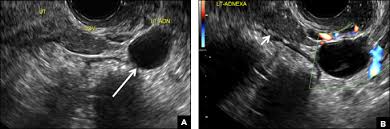

Female pelvis ultrasound sonography plays the primary role in imaging of the female pelvis. Primary indications for female pelvic us examination are pelvic pain, abnormal vaginal bleeding, and suspicion of pelvic mass. An ultrasound of the female pelvis may be performed by examination of the abdomen, called transabdominal, or by using a special probe designed to be inserted into the vagina, called transvaginal. Ultrasound imaging uses soundwaves to create pictures of the inside of the body. However, it is considered more invasive than the transabdominal approach. • normal and ectopic pregnancy implantation can be accurately Within the right ovary, there is a 2.5 cm thick walled cyst with crenulated inner margin and peripheral vascularity consistent with a corpus luteum. A transabdominal (ta) evaluation and a transvaginal (tv) / endovaginal (ev) evaluation. Further charac terization of a pelvic abnormality noted on another imaging study 14. A pelvic ultrasound is a noninvasive diagnostic exam that produces images that are used to assess organs and structures within the female pelvis. Measurements should be recorded for simple/complex/dermoid cysts. Transvaginal ultrasound is a test used to look at a woman's uterus, ovaries, tubes, cervix and pelvic area. Both ovaries should be identified and measured if appropriate again in 3 planes.

Within the right ovary, there is a 2.5 cm thick walled cyst with crenulated inner margin and peripheral vascularity consistent with a corpus luteum.

The left ovary measures __ x __ x __ cm in diameter and demonstrates normal vascular flow and echogenicity. Fed up with deciphering jargon, dr attiya khan asked consultant gynaecologist mr rehan khan for a plain language guide to understanding pelvic ultrasounds. A pelvic ultrasound is a safe procedure that can be slightly uncomfortable. Ultrasound imaging uses soundwaves to create pictures of the inside of the body. A pelvic ultrasound is a test that uses sound waves to make a picture of the inside of the lower belly (pelvis). Ct and mr are supplemental techniques used when the us examination is equivocal and in the staging of pelvic malignancy. The test can be done in two ways: No cysts are identified (a __ cm round, anechoic cyst is noted or normal follicles are identified).